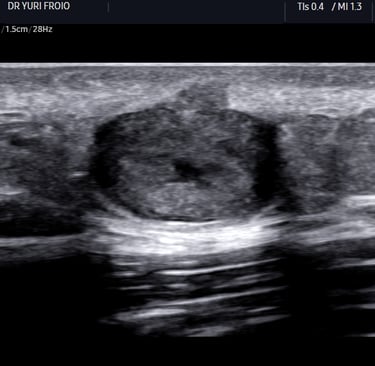

O ultrassom dermatológico é um exame não invasivo que utiliza ondas sonoras para visualizar as camadas da pele e estruturas subjacentes. Diferente dos exames convencionais, que utilizam frequências mais baixas, o ultrassom dermatológico emprega transdutores de alta frequência (acima de 15 MHz), proporcionando imagens de alta resolução da epiderme, derme e hipoderme.

A alta resolução das imagens permite diferenciar estruturas da pele, como epiderme, derme, hipoderme e possíveis lesões, facilitando a avaliação de tumores benignos e malignos, cistos, inflamações e outras alterações.